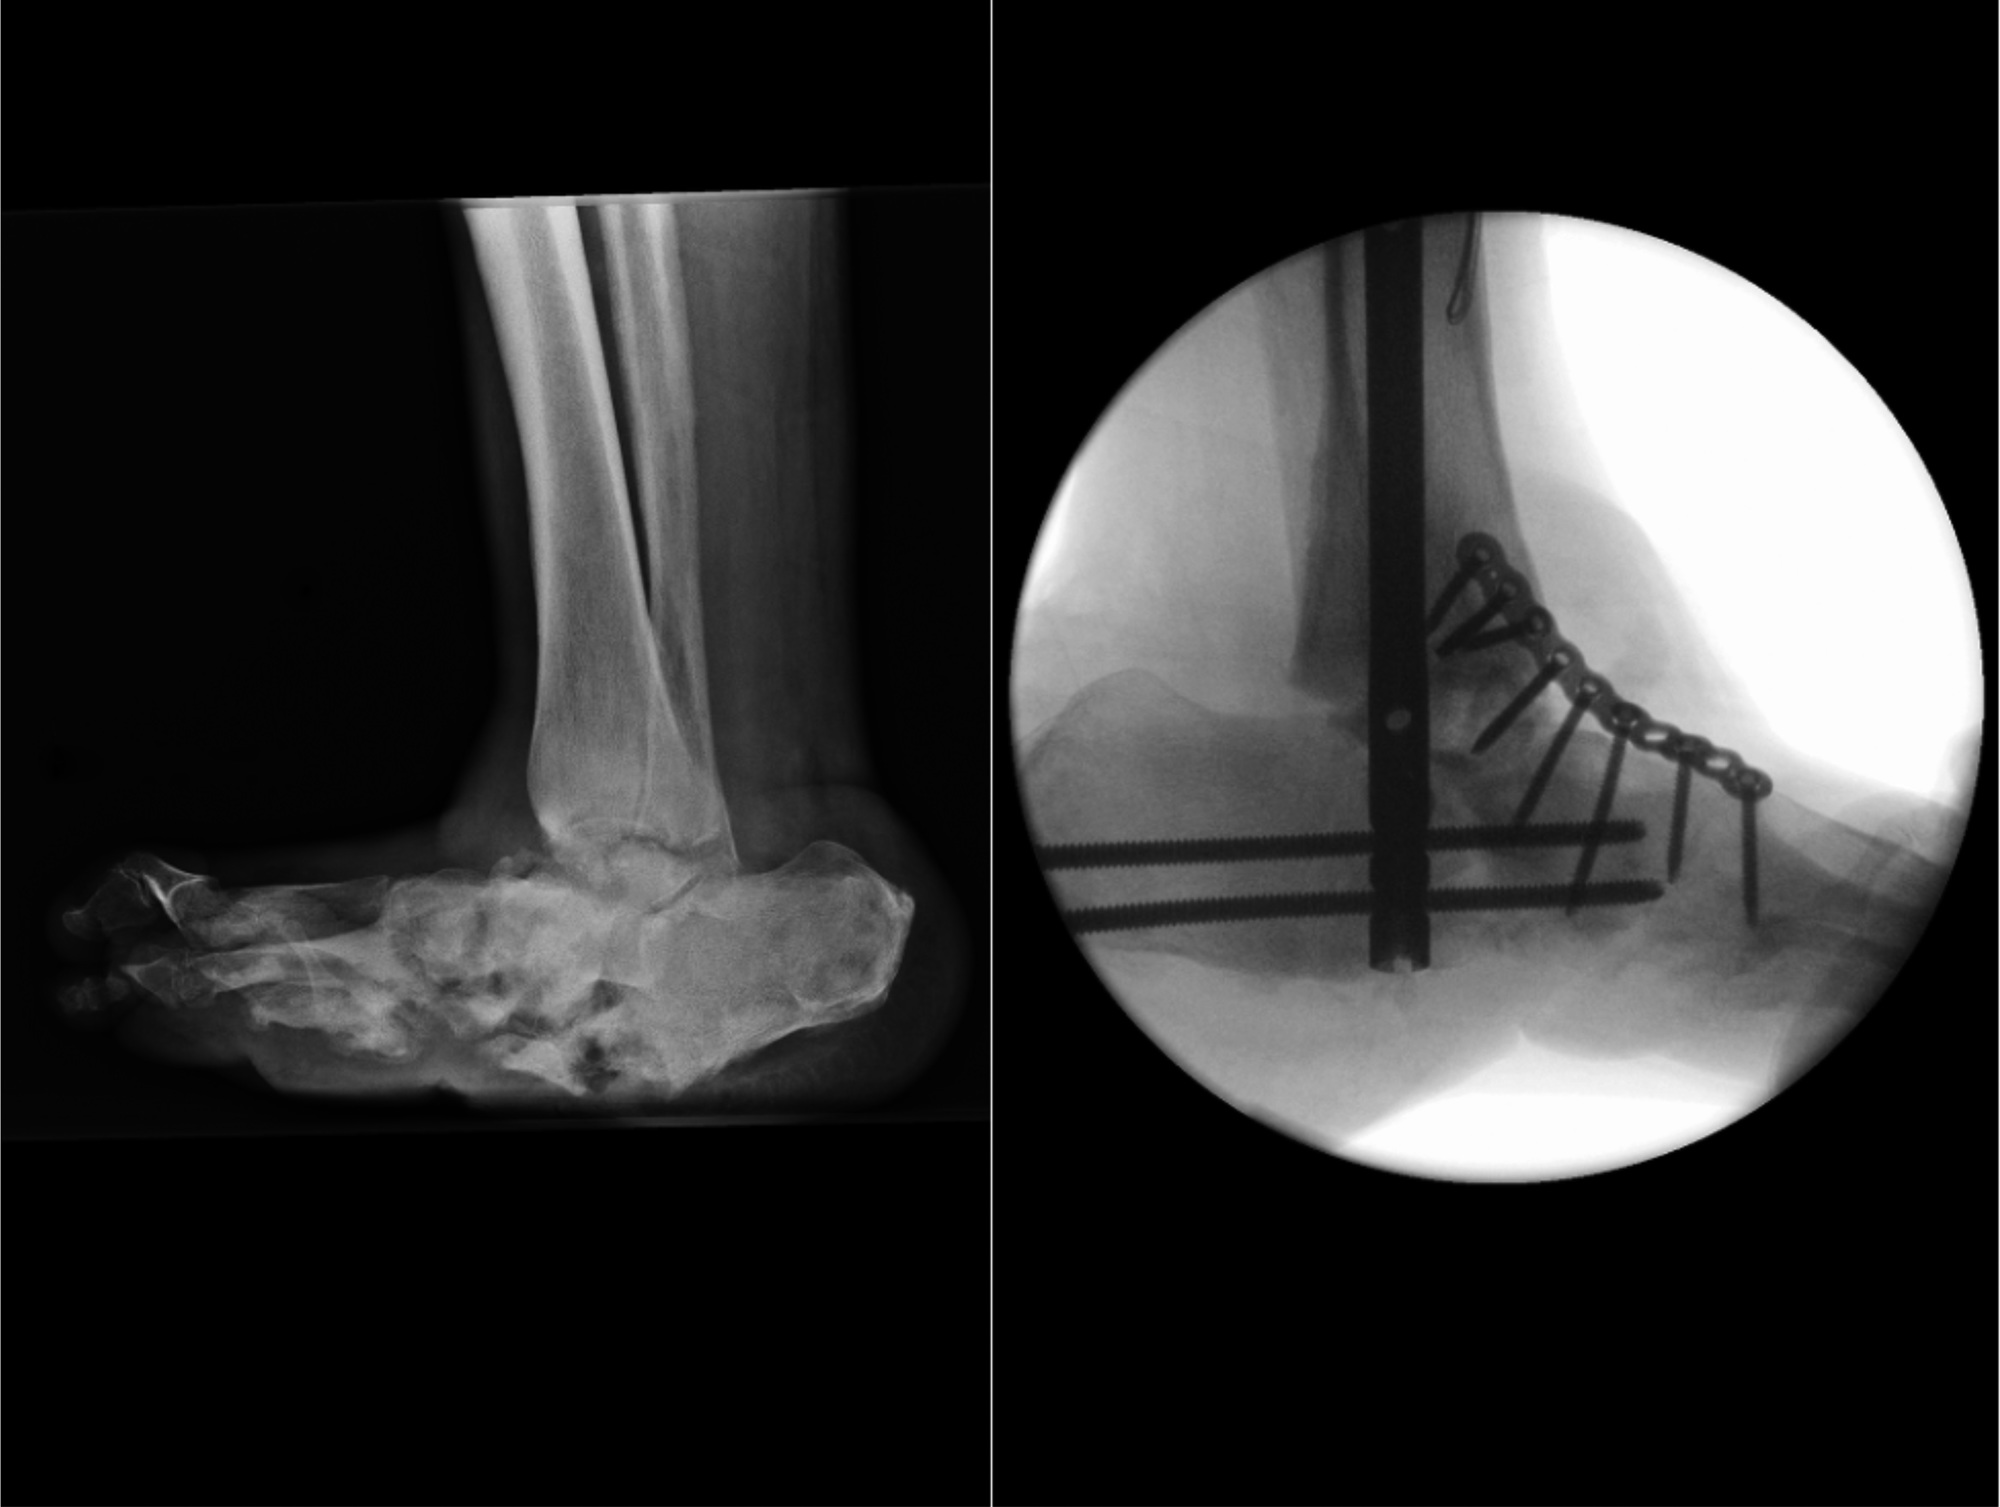

Figure 4. Left foot hind-foot and mid-foot reconstruction (right panel) for severe Charcot deformity (left panel). L, left; W/T, weight. ©KingsDFC

Injury to the diabetic neuropathic foot can trigger inflammation and aggressive osteolysis resulting in multiple fractures and bone fragmentations. Ongoing research has focused on understanding the pathogenic mechanisms driving such activity, such as the osteoclastogenic cytokine receptor activator of nuclear factor-κβ ligand RANKL, and on exploring the role of proinflammatory cytokines such as tumour necrosis factor-α. This raises the potential of future putative pharmacologic therapeutic options, something we lack currently. Contemporary orthopaedic reconstruction techniques offer a new hope to those with gross deformities and facing amputation (Figure 4).